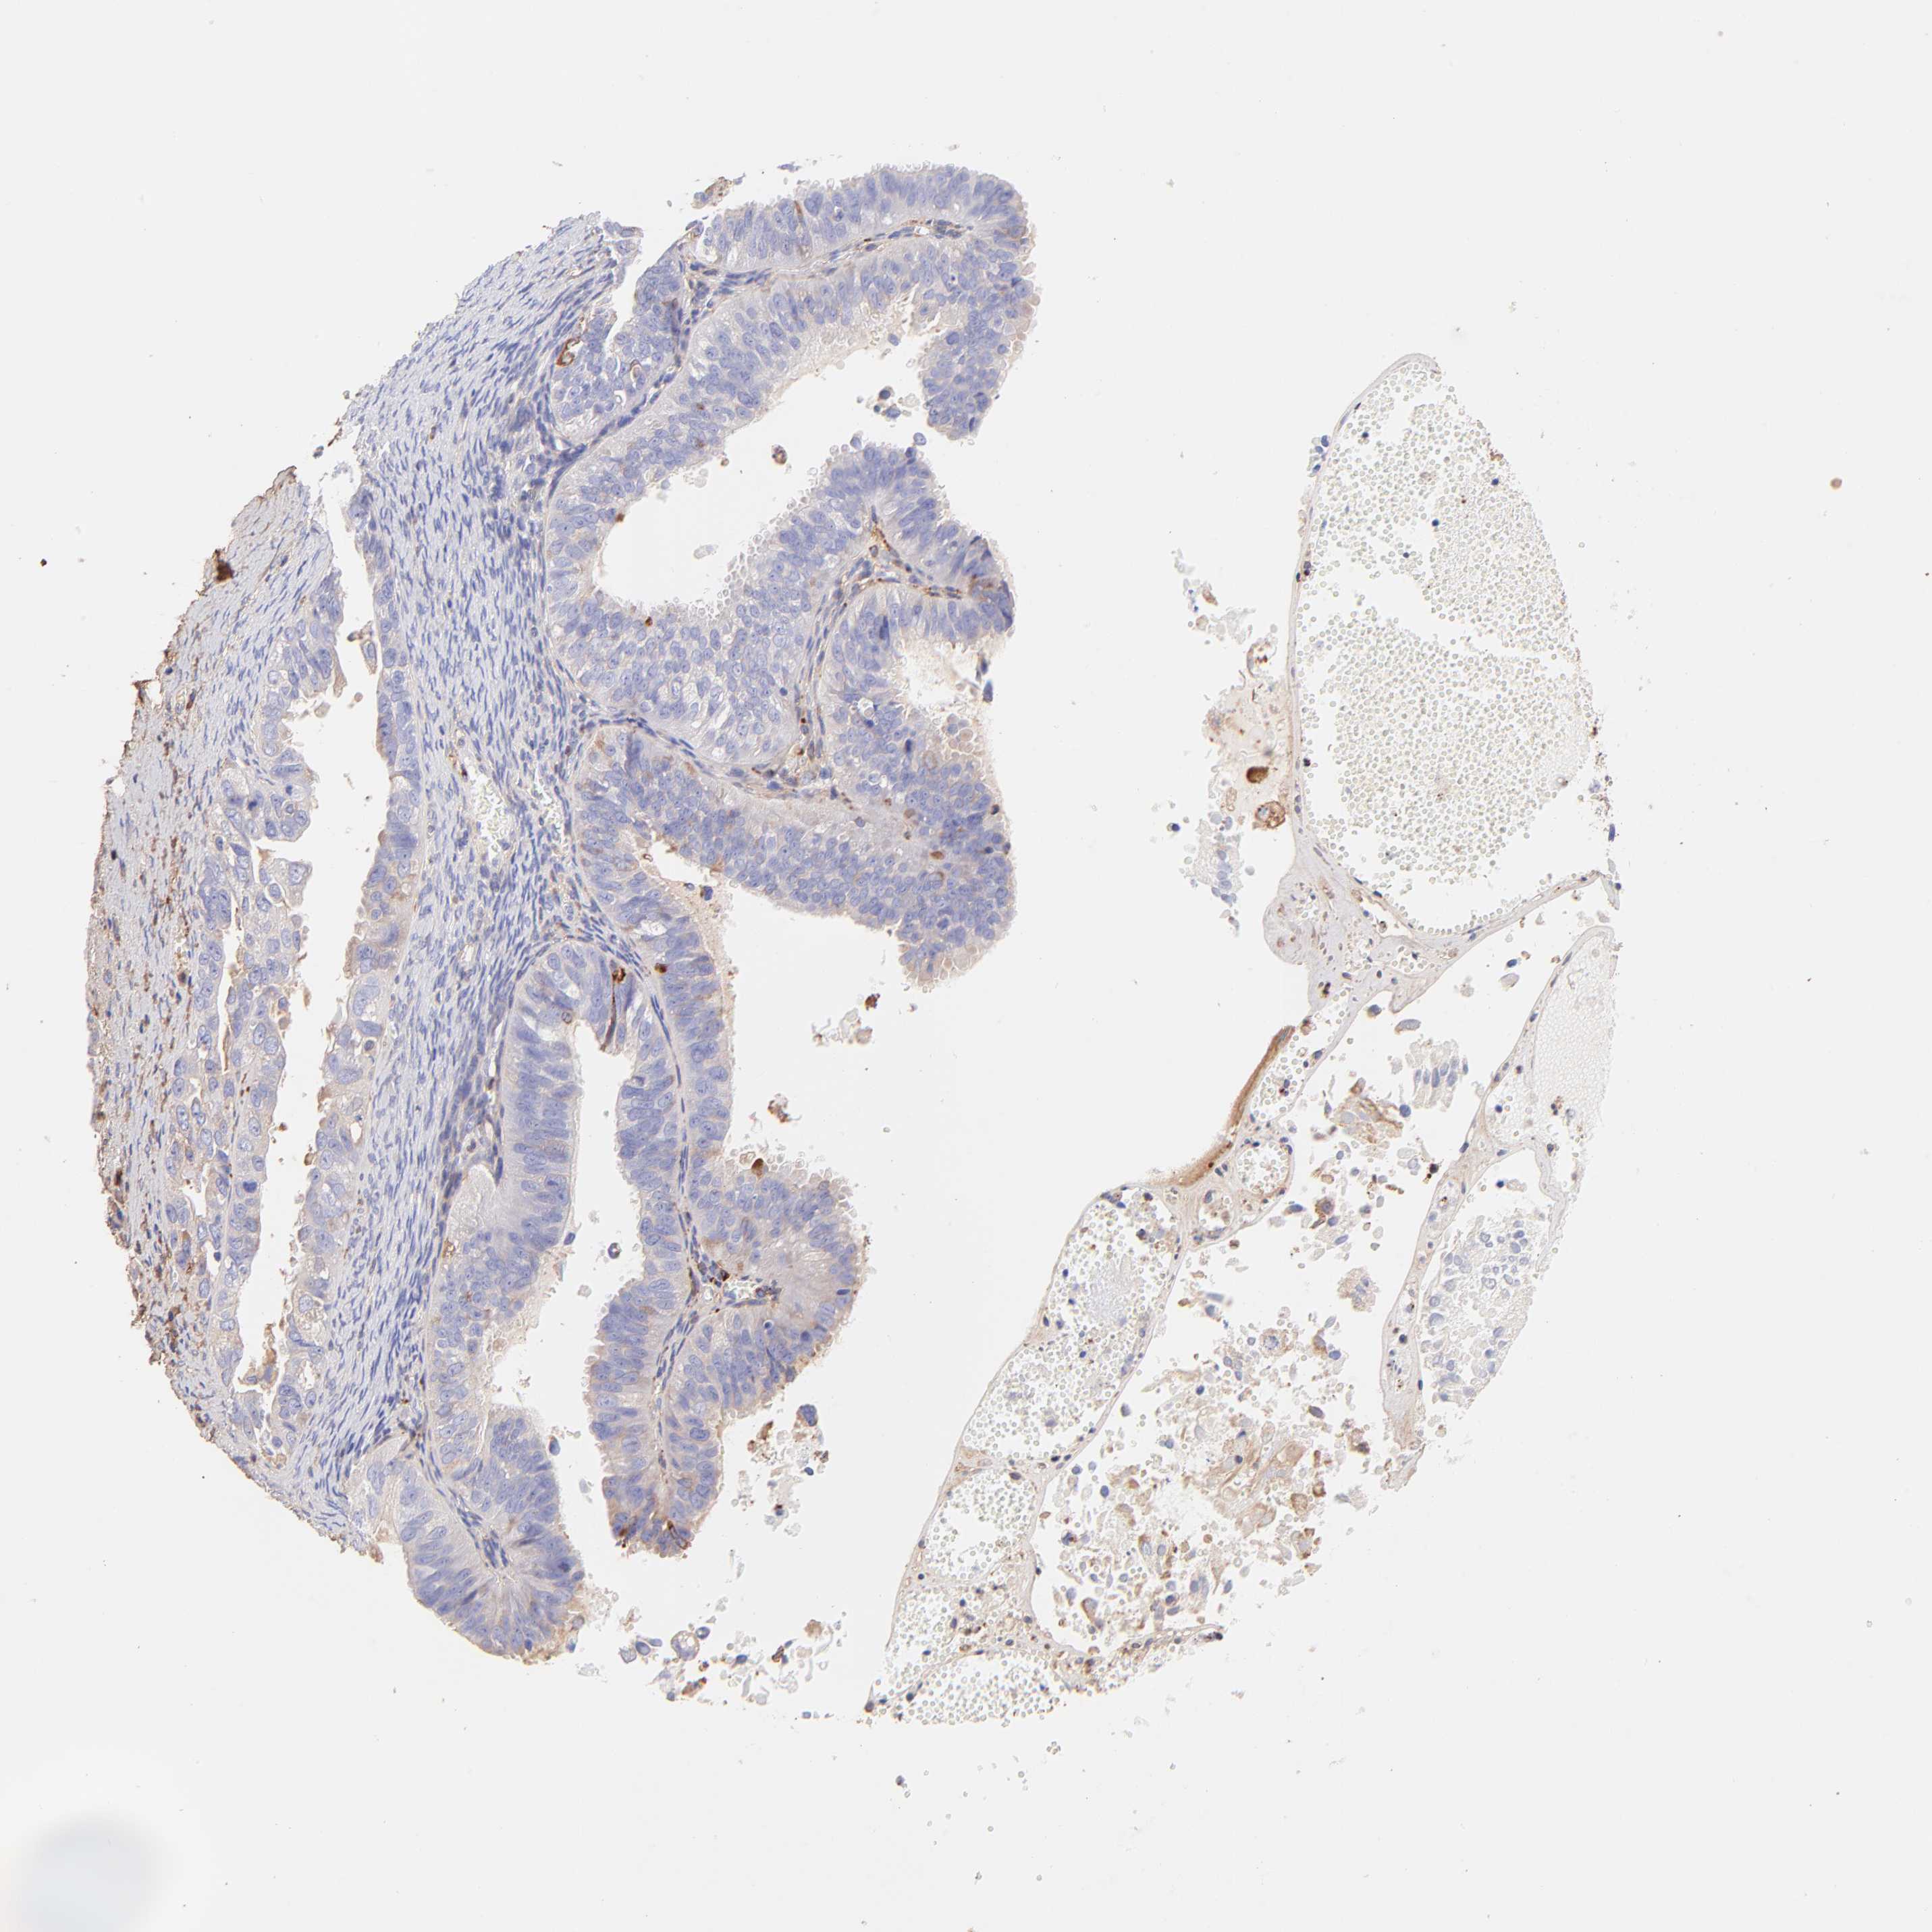

OVARIAN CANCER - Protein expressioni

A mouse-over function shows sample information and annotation data. Click on an image to view it in a full screen mode. Samples can be filtered based on level of antibody staining by selecting one or several of the following categories: high, medium, low and not detected. The assay and annotation is described here.

Note that samples used for immunohistochemistry by the Human Protein Atlas do not correspond to samples in the TCGA dataset.

Antibody stainingi

Antibody staining in the annotated cell types in the current human tissue is reported as not detected, low, medium, or high, based on conventional immunohistochemistry profiling in selected tissues. This score is based on the combination of the staining intensity and fraction of stained cells.

Each image is clickable and will lead to virtual microscopy that enables deeper exploration of all samples and also displays staining intensity scores, fraction scores and subcellular localization as well as patient and tissue information for each sample.

Antibody HPA003157

Antibody CAB003678

Staining

High

Medium

Low

Not detected

Intensity

Strong

Moderate

Weak

Negative

Quantity

>75%

75%-25%

<25%

None

Location

Nuclear

Cytoplasmic/membranous

Cytoplasmic/membranous,nuclear

Carcinoma, endometroid

Cystadenocarcinoma, serous, NOS

Cystadenocarcinoma, mucinous, NOS